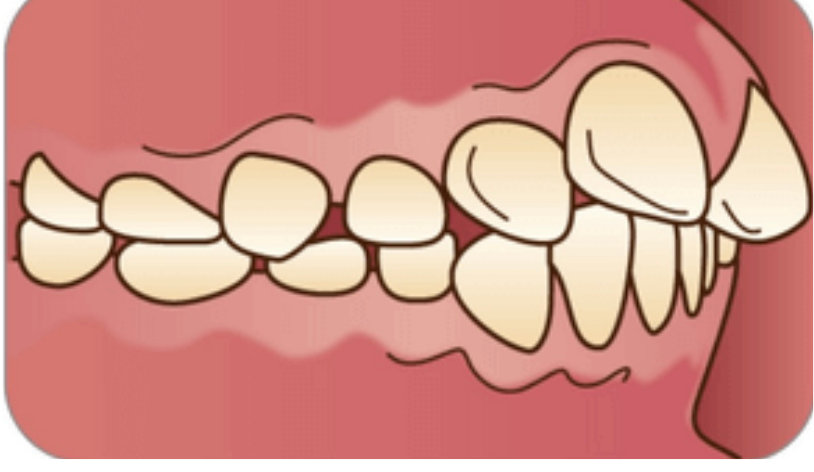

上顎前突(じょうがくぜんとつ)/出っ歯

前歯が出ている